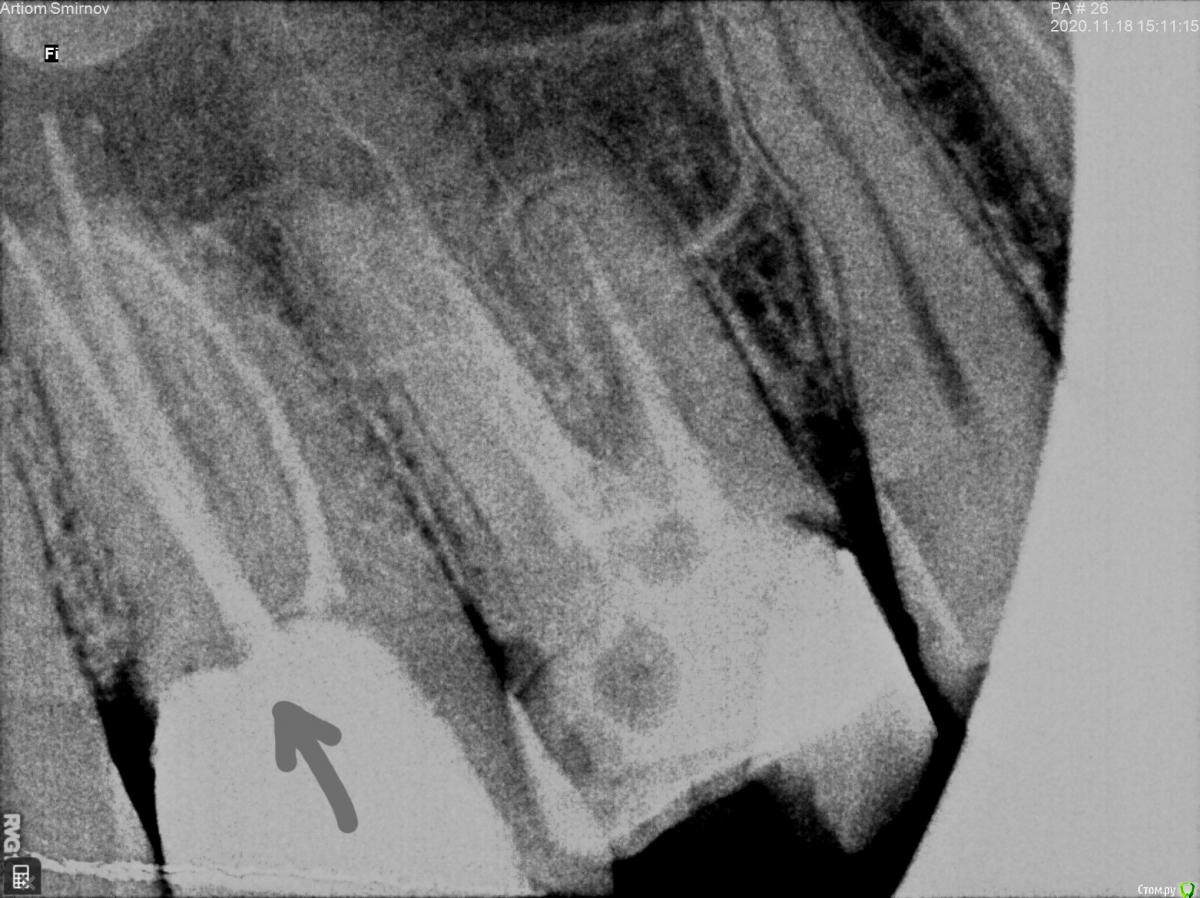

Artiom_Kl Опубликовано 26 ноября, 2020 Поделиться Опубликовано 26 ноября, 2020 Доброго времени суток! Буду очень Вам признателен, если дадите совет. Ситуация такова: Стоматолог запломбировал 3 канала и поставил временную пломбу (на месяц, до следующего приема, когда он должен уже поставить постоянную пломбу). Однако уже 3 недели, как я испытываю практически постоянный дискомфорт в зубе, который на 2 неделе уже перерос в ноющую боль, хоть и незначительную и не постоянную (сейчас уже 3 неделя-ситуация без изменений). Обратился к стоматологу. Он посмотрел визуально ротовую полость и сказал, что всё нормально, боль какое-то время может быть. И, по его словам, после установки постоянной пломбы боль через некоторое время должна исчезнуть. Нерв, как он добавил, беспокоить не может, так как он его умертвил. Однако меня терзают сомнения, что каналы запломбированы качественно. Я запросил у него снимки, сделанные после пломбирования каналов. Взгляните, пожалуйста, на рентгеновские снимки. Можно ли по ним судить о качестве пломбирования каналов ? Ссылка на комментарий